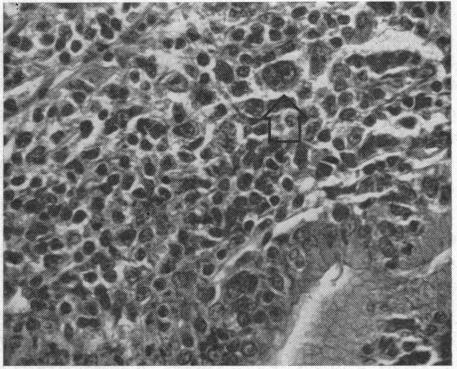

Acalculous cholecystis due to Hodgkin's disease.

Calif Med. 1970 Mar;112(3):28-30.

PMID:5451611

原文链接:https://pmc.ncbi.nlm.nih.gov/articles/PMC1501418/